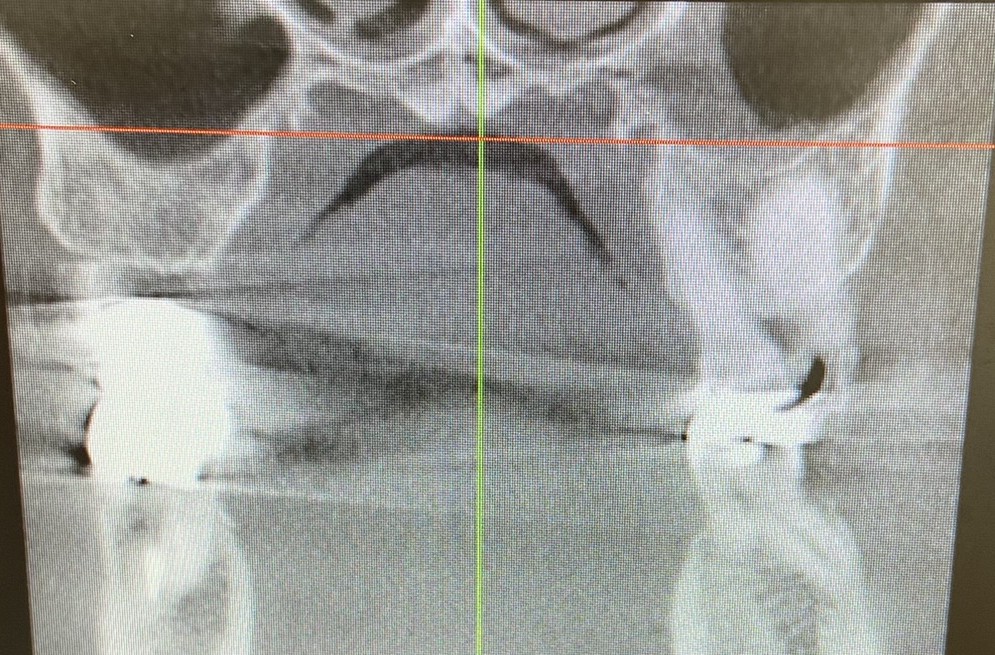

必要に応じて、耳鼻科でCT検査を依頼し、上顎洞の状態を詳しく調べることもあります。